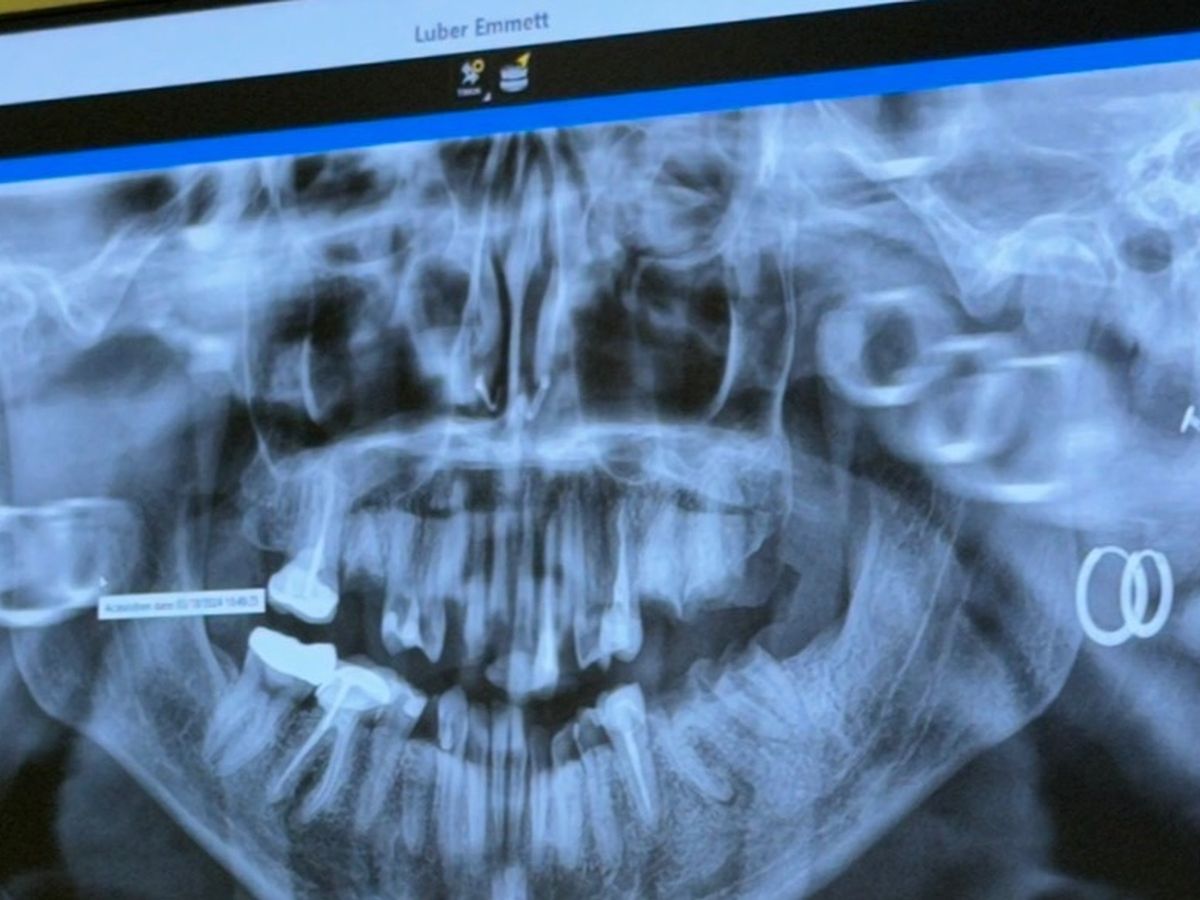

Hi, I’m Emmett. I have a genetic condition called Ehlers Danlos that can cause increased dental decay. On top of that, I went through a severe mental health battle a few years ago and I didn’t get my teeth taken care of during that time because I expected to be dead by 25.

I’m 27 now and I have to get my teeth taken care of before the infection, that I have had in multiple teeth for quite some time, travels to my brain. I need all of my teeth extracted and then either dentures or implants, if I can somehow afford them.

My goal is set for the minimum, which will get my teeth extracted and give me dentures. Ideally I’d like to get implants which would be $18,290 so that my bone loss is minimal, but if I can at least get my dentures that would be a huge help. I have bad credit and don’t qualify for loans, so this is pretty much my last resort. I hate asking here, but I don't want to die of a brain infection before I get the chance to turn 30, and I don’t have any other options.